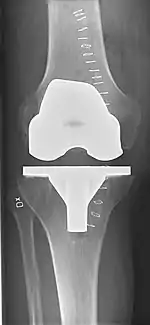

Knee replacement, also known as knee arthroplasty, is a surgical procedure to replace the weight-bearing surfaces of the knee joint to relieve pain and disability, most commonly offered when joint pain is not diminished by conservative sources.[1][2] It may also be performed for other knee diseases, such as rheumatoid arthritis. In patients with severe deformity from advanced rheumatoid arthritis, trauma, or long-standing osteoarthritis, the surgery may be more complicated and carry higher risk. Osteoporosis does not typically cause knee pain, deformity, or inflammation, and is not a reason to perform knee replacement.

Knee replacement surgery can be performed as a partial or a total knee replacement.[3] In general, the surgery consists of replacing the diseased or damaged joint surfaces of the knee with metal and plastic components shaped to allow continued motion of the knee.